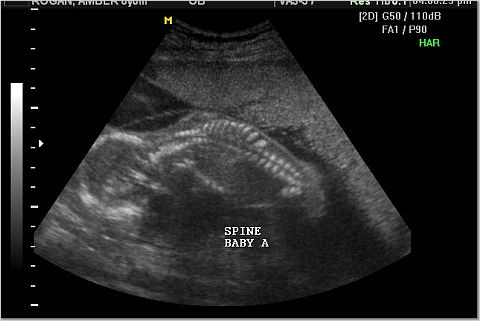

We went to Ultrasona in O'Fallon on Saturday, July 23rd (after the ultrasound with the doctor)

and found out that one of the babies is a girl! We went back on Tuesday, July 26th

and found out they are both girls!

IT'S 2 GIRLS!!!

Baby A and Baby B Spine

Baby A was the active one. Here is her profile and her hand.